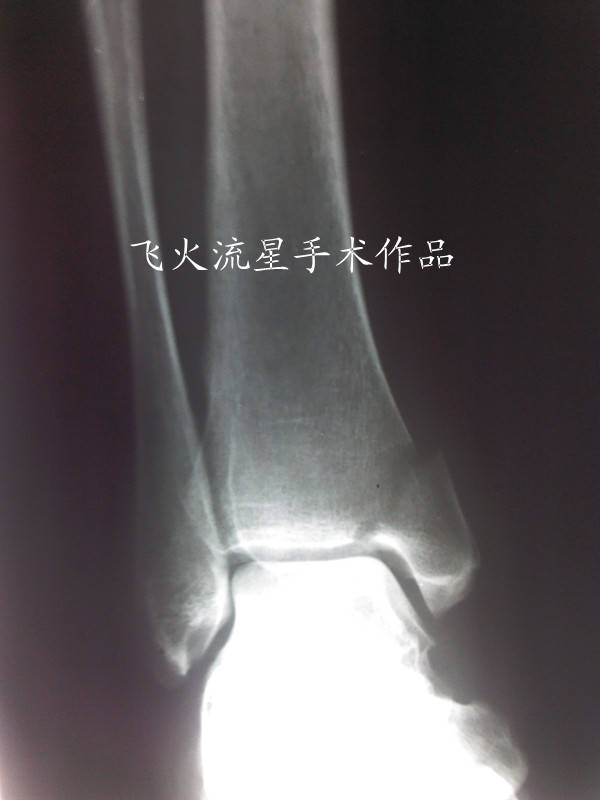

内踝进钉前术者应该用了骨钻打空,估计是怕打进关节腔吧,所以打的高了些再或是暴露不够。

其实内踝用普通松质骨螺钉固定时可以不用骨钻,直接用2.0或2.5的克氏针做一个锥子复位后直接在上面钻孔后拧钉即可。此办法简单有效,本人一直在使用,效果很好。